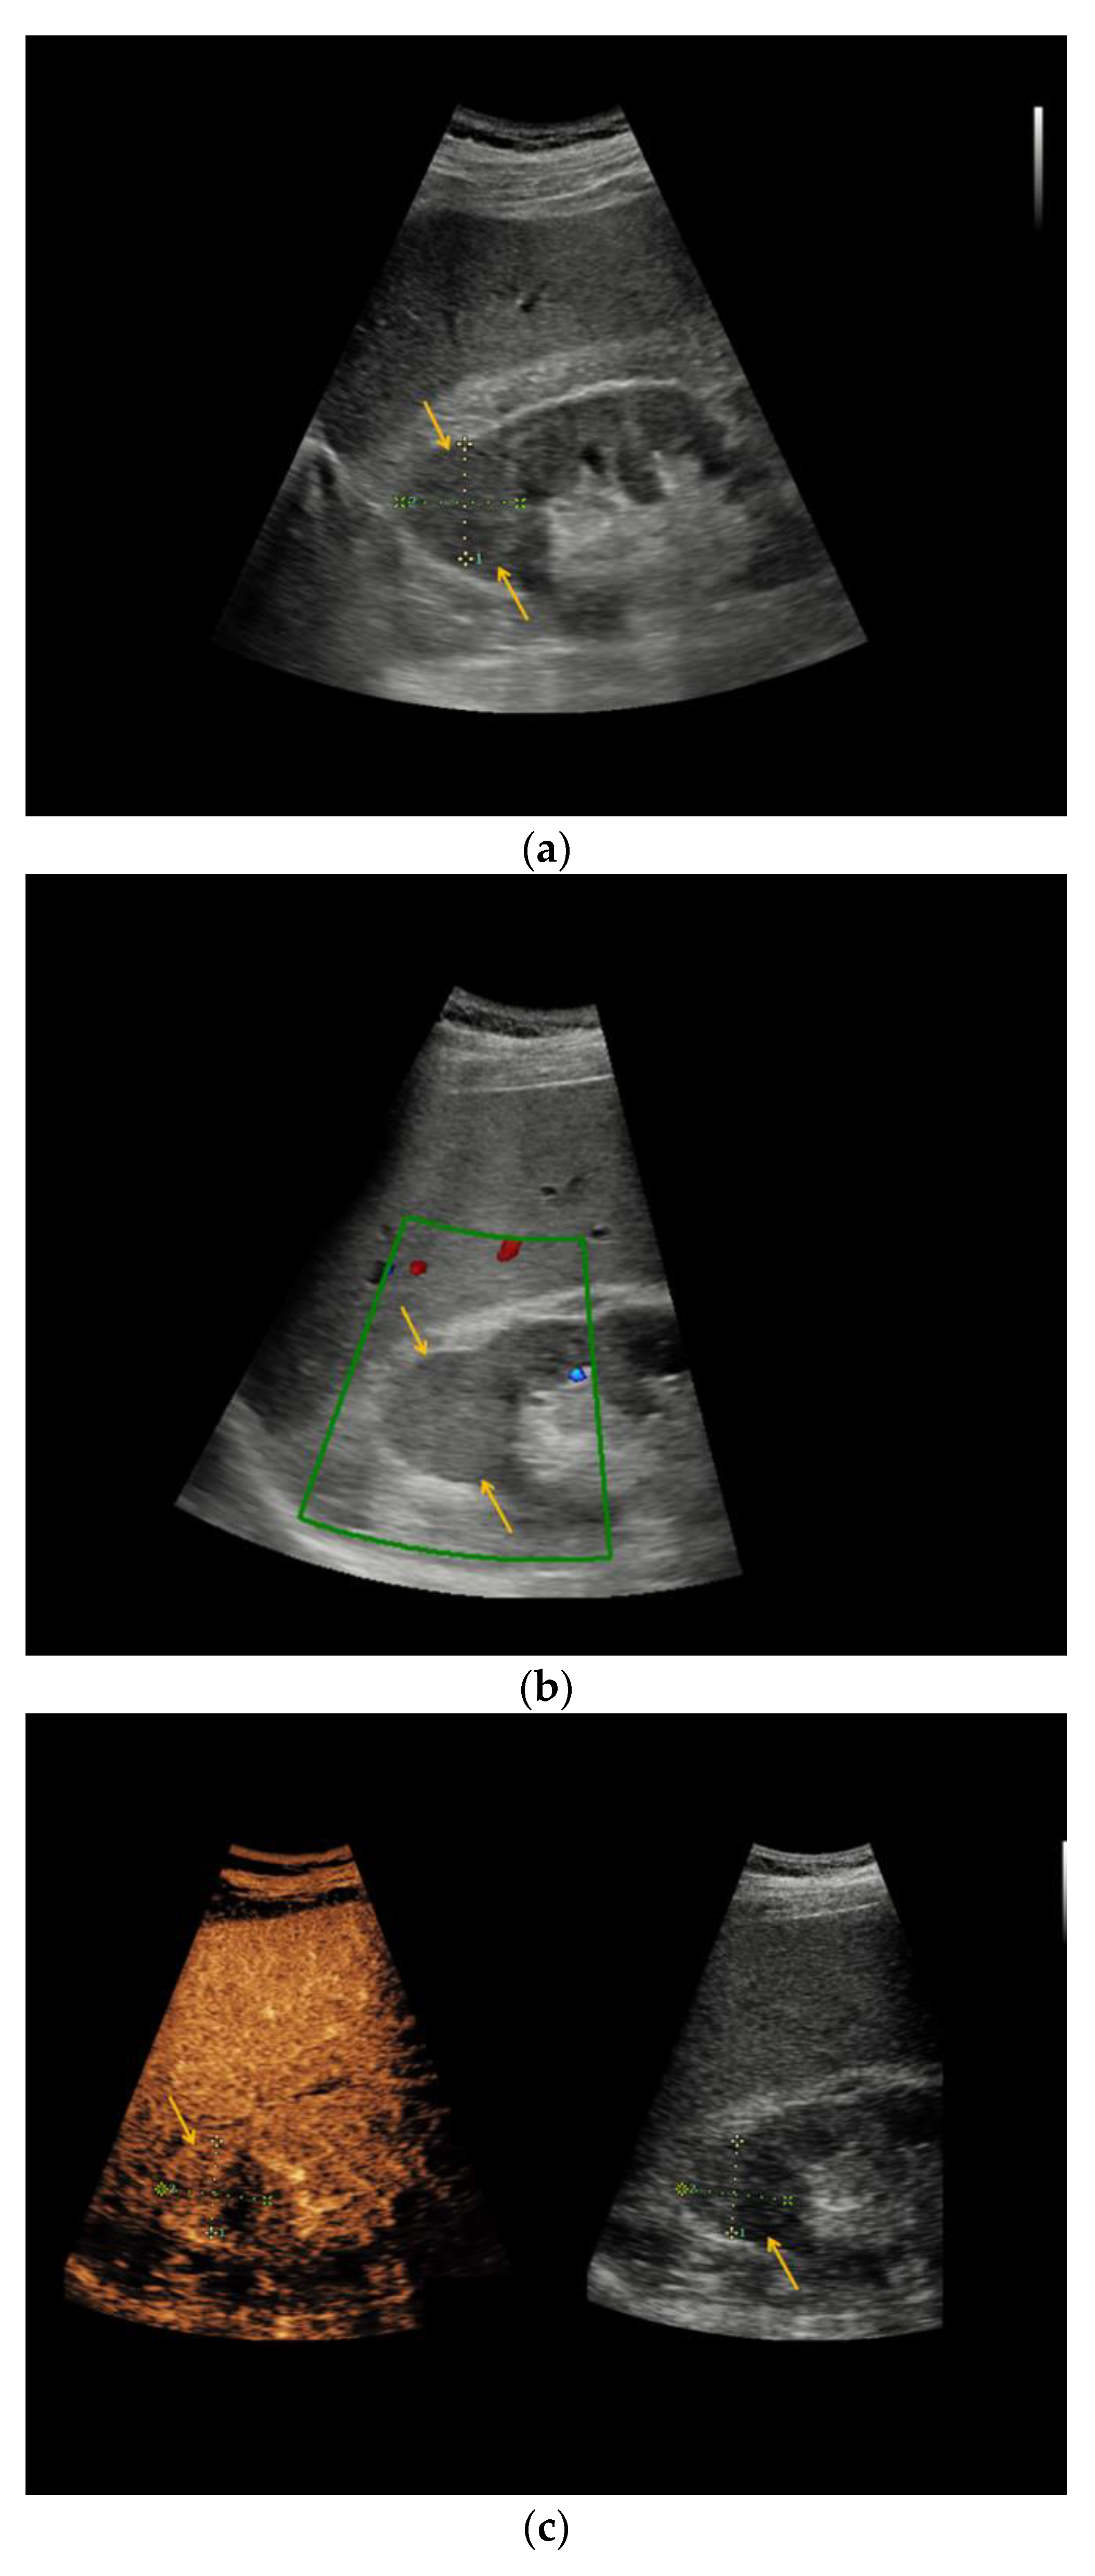

| Patient | Sex | Age | Location | Size (cm) | Native B-Mode | Vascularization (CD) | CEUS | CT | MRI | Treatment: Histopathology |

|---|---|---|---|---|---|---|---|---|---|---|

| #1 | F | 49 | R | 5.6 | Cystic, septated | - | Intraseptal | - | Intraseptal enhancing → Bosniak IIF | Partial nephrectomy: Clear-cell RCC |

| #2 | M | 54 | L | 3.0 | Cystic, hypoechoic areas, wall thickening | - | Peripheral | - | - | Partial nephrectomy: chromophobe RCC |

| #3 | F | 61 | R | 3.5 | Cystic, septated | - | Peripheral, intraseptal | - | - | Partial nephrectomy: clear-cell RCC |

| #4 | F | 43 | R | 1.6 | Cystic | - | Peripheral | - | - | Partial nephrectomy: clear-cell RCC |

| #5 | F | 64 | L | 5.0 | Cystic, focally thickened, septa | - | Intraseptal | - | - | Partial nephrectomy: clear-cell partial cystic RCC |

| #6 | M | 74 | L | 2.0 | Cystic | - | Peripheral, intraseptal | - | - | Partial nephrectomy: clear-cell RCC |

| #7 | F | 66 | L | 7.0 | Cystic, complex | - | Intraseptal | - | - | Partial nephrectomy: multilocular cystic RCC |

| #8 | M | 54 | L | 1.5 | Cystic, wall thickening | - | Intraseptal | - | - | Partial nephrectomy: clear-cell RCC |

| #9 | M | 76 | L | 1.6 | Cystic | - | Peripheral, wash-out | - | - | Partial nephrectomy: papillary RCC |

| #10 | F | 66 | R | 1.5 | Cystic | - | Intraseptal | - | - | Partial nephrectomy: clear-cell RCC |

| #11 | M | 75 | L | 2.7 | Cystic, focally thickened septa | - | Intraseptal | - | - | Partial nephrectomy: Papillary RCC |

| #12 | M | 52 | L | 1.5 | Cystic, focally thickened septa | - | Intraseptal | - | - | Partial nephrectomy: clear-cell RCC |

| #13 | M | 68 | L | 1.5 | Partially cystic | - | Peripheral | - | - | Partial nephrectomy: clear-cell RCC |

| #14 | M | 86 | L | 4.0 | Cystic, septated | - | Intraseptal | Septated, calcified, early enhancement, wash-out in delayed phase → Bosniak III | - | Nephrectomy: cystic clear-cell RCC |

| #15 | M | 63 | R | 2.0 | Cystic | - | Peripheral | - | - | Nephrectomy: clear-cell RCC |

| #16 | F | 62 | L | 2.5 | Partially cystic | - | Peripheral, intraseptal wash-in/wash-out | - | Native MRI: T2w: mainly hyperintense with hypointense septations T1w: hypointense | Renal biopsy: oncocytoma |

| #17 | F | 64 | R | 3.5 | Cystic | - | Intraseptal | - | - | Partial nephrectomy: cystic hamartoma |

| #18 | M | 67 | R | 3.0 | Partially cystic, focally thickened septa | - | Intraseptal | - | - | Partial nephrectomy: cyst, no malignancy |

| #19 | M | 71 | L | 1.2 | Cystic | - | Peripheral | - | - | Partial nephrectomy: cyst, no malignancy |

| #20 | F | 48 | L | 10.0 | Cystic, septated | - | Intraseptal | - | - | Partial nephrectomy: adult cystic nephroma |

| #21 | M | 76 | R | 2.0 | Cystic | - | Peripheral and Intraseptal wash-in/wash-out | - | - | Partial nephrectomy: oncocytoma |

| #22 | M | 46 | R | 0.8 | Cystic | - | Peripheral wash-in/wash-out | - | - | Partial nephrectomy: papillary adenoma |

| #23 | F | 69 | L | 8.0 | Cystic, septated | - | Intraseptal | - | - | Partial nephrectomy: cyst, no malignancy |

| #24 | M | 69 | R | 2.5 | Cystic | - | Peripheral wash-in/wash-out | - | - | Partial nephrectomy: Papillary RCC |

| #26 | M | 66 | R | 5.0 | Cystic | - | Peripheral | - | - | Partial nephrectomy: Hemorrhagic, xantho-granulomatous cyst, no malignancy |

| #27 | M | 67 | R | 7.0 | Cystic, septated, partially calcified | - | Peripheral, intraseptal | Septated, partially calcified → Bosniak IIF | - | Partial nephrectomy: oncocytoma |

| #32 | M | 83 | L | 4.7 | Cystic | - | Peripheral | - | - | Partial nephrectomy: clear-cell RCC |

| #35 | M | 48 | R | 2.5 | Cystic, septated | - | Intraseptal wash-in/wash-out | - | - | Partial nephrectomy: clear-cell RCC |

| #38 | M | 60 | R | 1.2 | Cystic, septated | - | Peripheral | Septated, contrast-enhanced → Bosniak type IIF | - | Partial nephrectomy: clear-cell RCC |